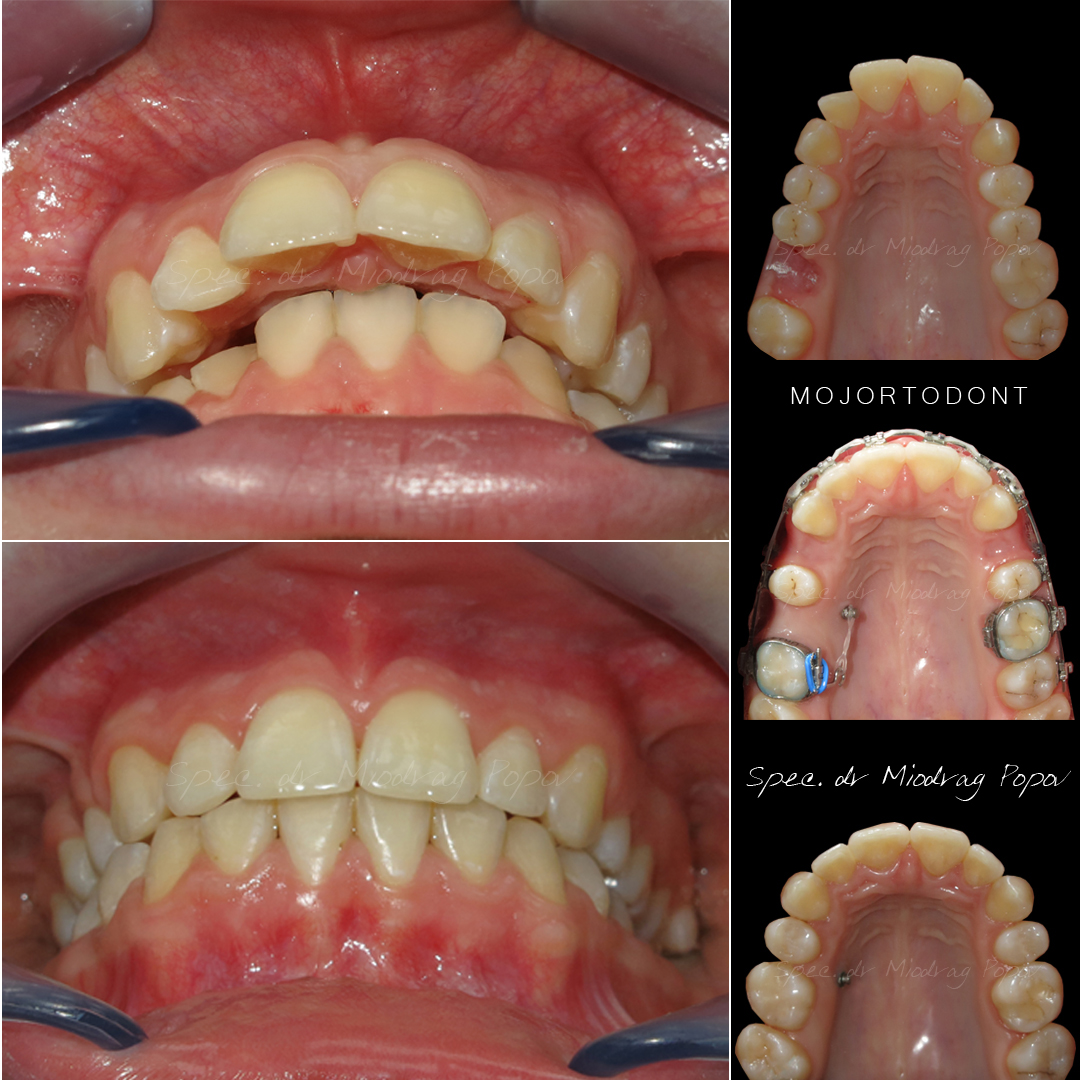

Slučaj ortodontske terapije II klase s vađenjem gornjih prvih predkutnjaka.

Na početku terapije, pacijentkinja je već imala izvađen gornji prvi kutnjak.

Tokom tretmana, svi prostori su zatvoreni, a profil lica transformisan.

Rezultat? Jasno definisana brada i harmoničan profil!